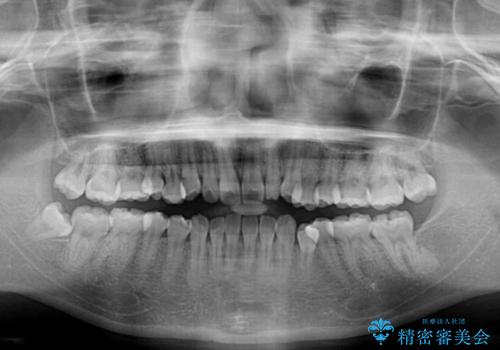

- 患者様は「歯並び全体のデコボコが気になり、人前で笑うことに抵抗がある」とのことでご来院されました。

診査の結果、上下顎ともに叢生が認められましたが、ワイヤー矯正・マウスピース矯正のいずれでも対応可能な症例でした。